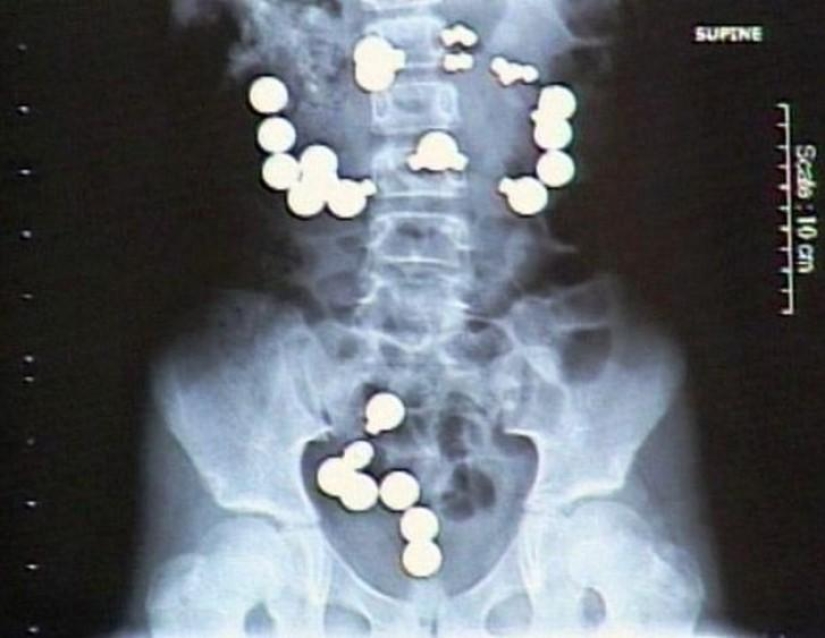

4. Coins.